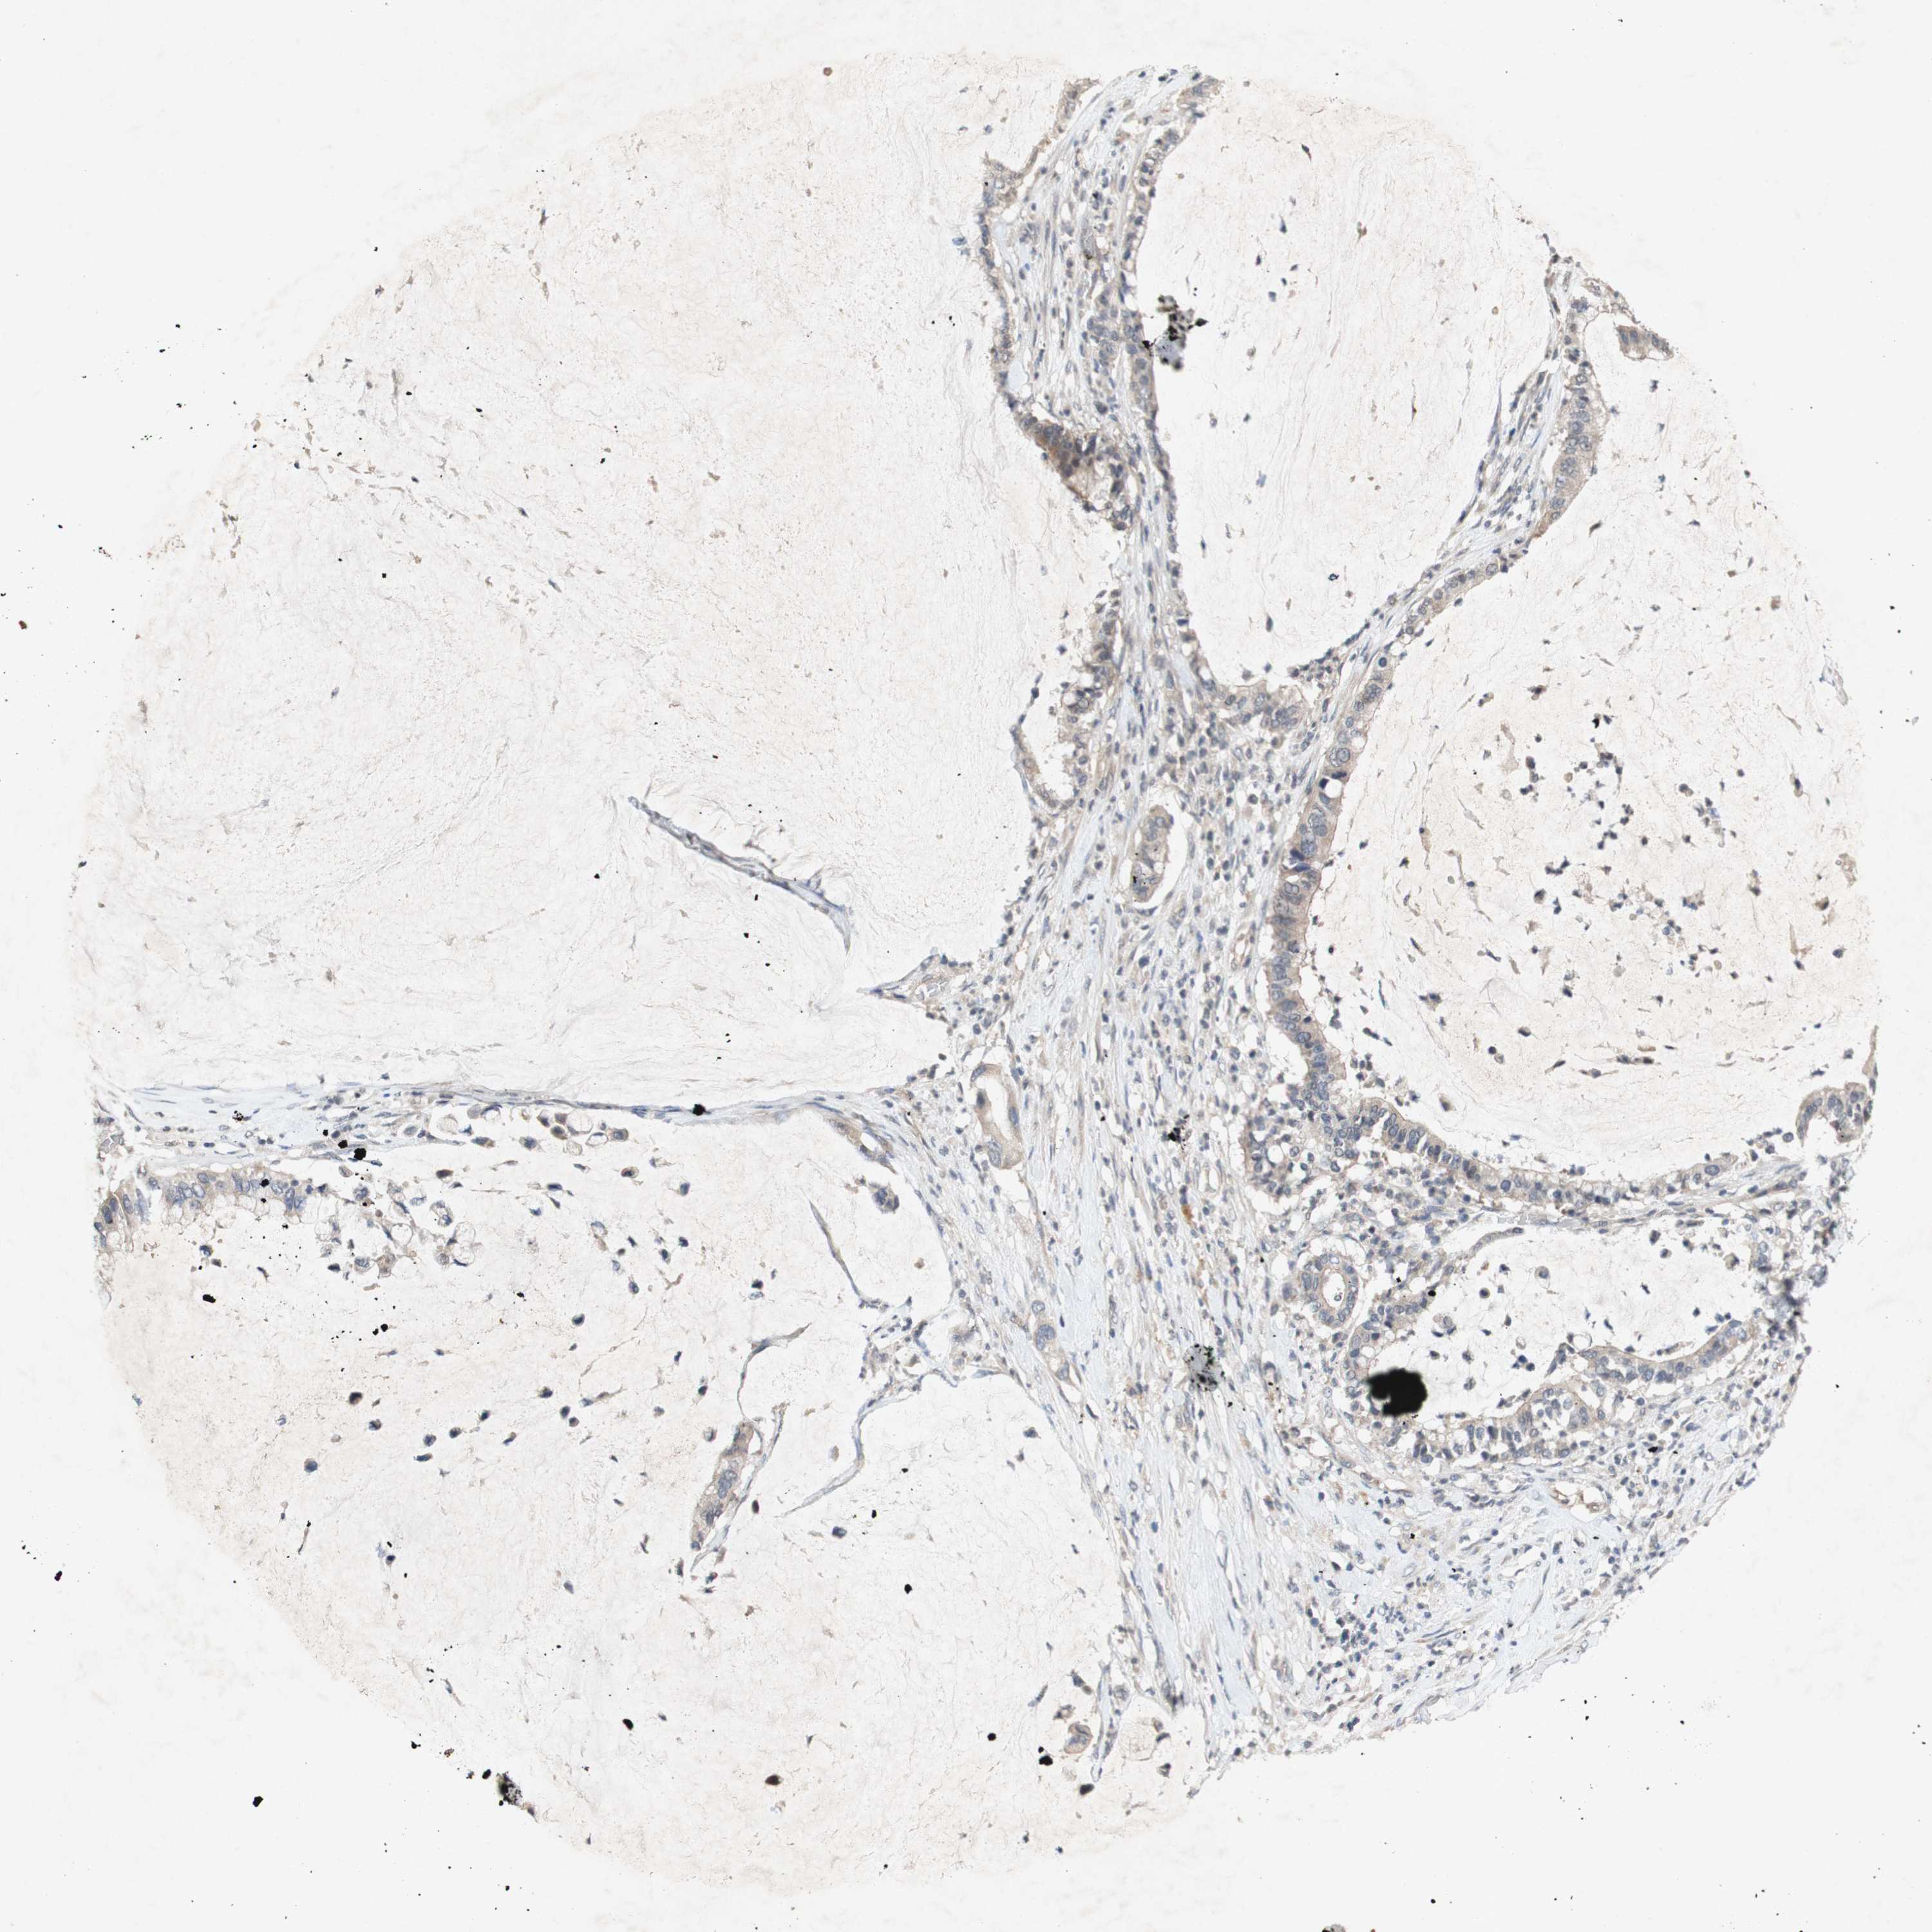

PANCREATIC CANCER - Protein expressioni

A mouse-over function shows sample information and annotation data. Click on an image to view it in a full screen mode. Samples can be filtered based on level of antibody staining by selecting one or several of the following categories: high, medium, low and not detected. The assay and annotation is described here.

Note that samples used for immunohistochemistry by the Human Protein Atlas do not correspond to samples in the TCGA dataset.

Antibody stainingi

Antibody staining in the annotated cell types in the current human tissue is reported as not detected, low, medium, or high, based on conventional immunohistochemistry profiling in selected tissues. This score is based on the combination of the staining intensity and fraction of stained cells.

Each image is clickable and will lead to virtual microscopy that enables deeper exploration of all samples and also displays staining intensity scores, fraction scores and subcellular localization as well as patient and tissue information for each sample.

Antibody CAB004528

Antibody CAB009326

Adenocarcinoma, NOS